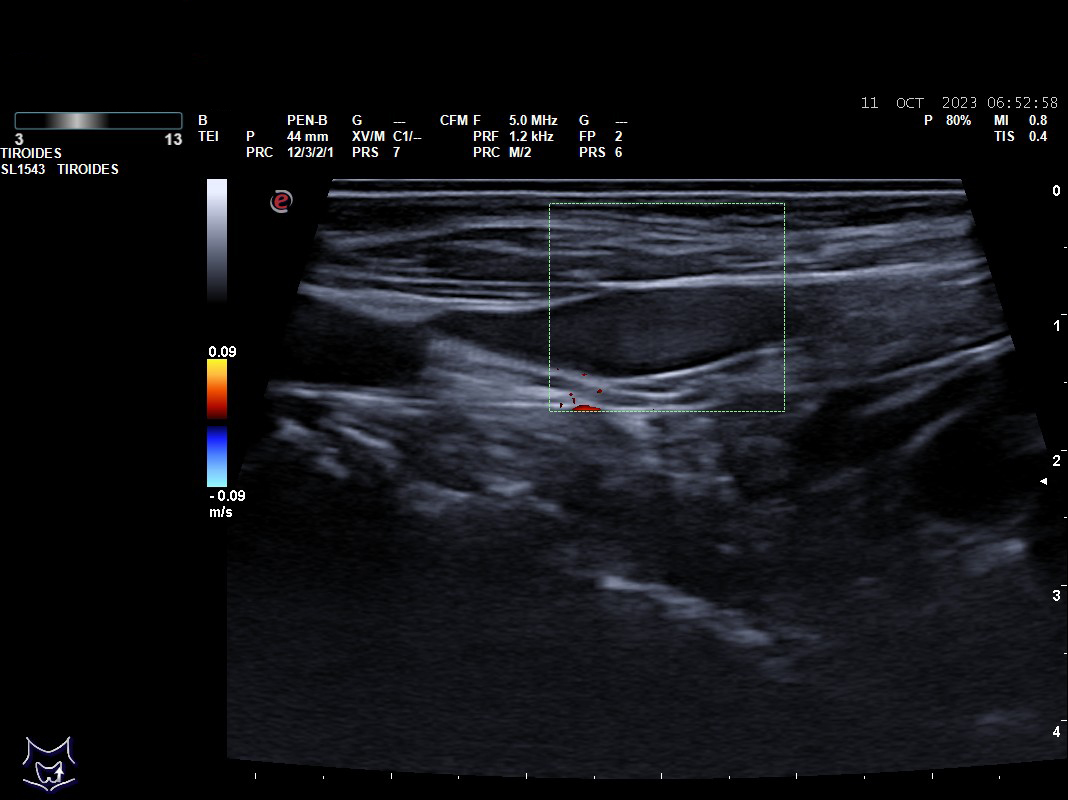

Hallazgos ecográficos: nódulos tiroideos subcentimétricos sin cambios, yugular interna izda con contenido discretamente hiperecogénico que no capta Doppler y colapsabilidad incompleta.

Se deriva a urgencias es valorada por cirugía vascular quienes describen la presencia del trombo sin poder precisar su final y se ingresa a la paciente ya que el servicio de radiología no considera realizar en ese momento el estudio pertinente.

Tras cinco días de ingreso se realiza un ecodoppler reglado descartándose la trombosis venosa, se suspende la anticoagulación y se da de alta sin tratamiento.